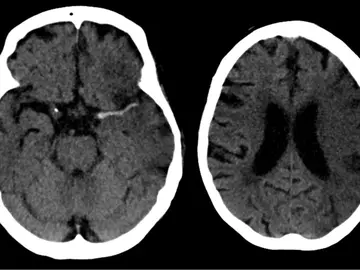

El ictus cerebral mata las neuronas mediante ondas eléctricas letales